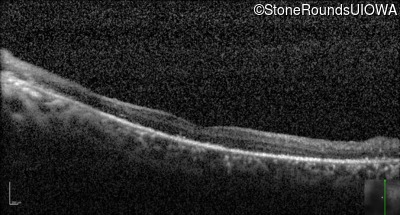

Optical Coherence Tomography - Right - 20/1000 sc

Exemplar / OCT Stack

Optical Coherence Tomography - Left - 20/500 sc